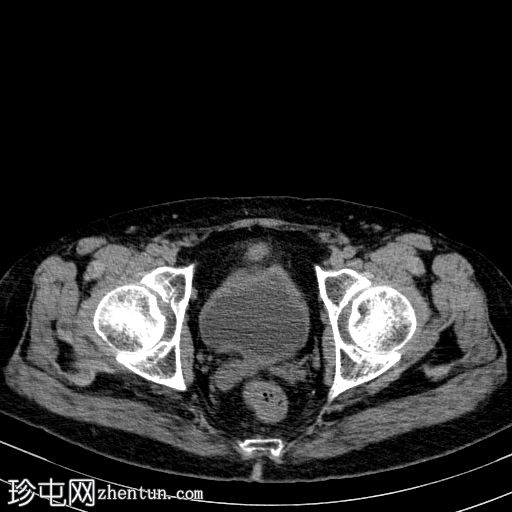

轴向

非造影

胰体尾弥漫性增大,特征为胰腺实质低强化,无明显坏死区域。

胰周筋膜平面边界不清的污迹,无明显壁形成、气室、固体碎片或血液产物。

病变横向延伸至左前肾旁间隙,伴有Gerota筋膜增厚。

病变向下延伸至盆腔。

无肠系膜或脾脏血管阻塞的证据。

未见导管扩张或钙化。